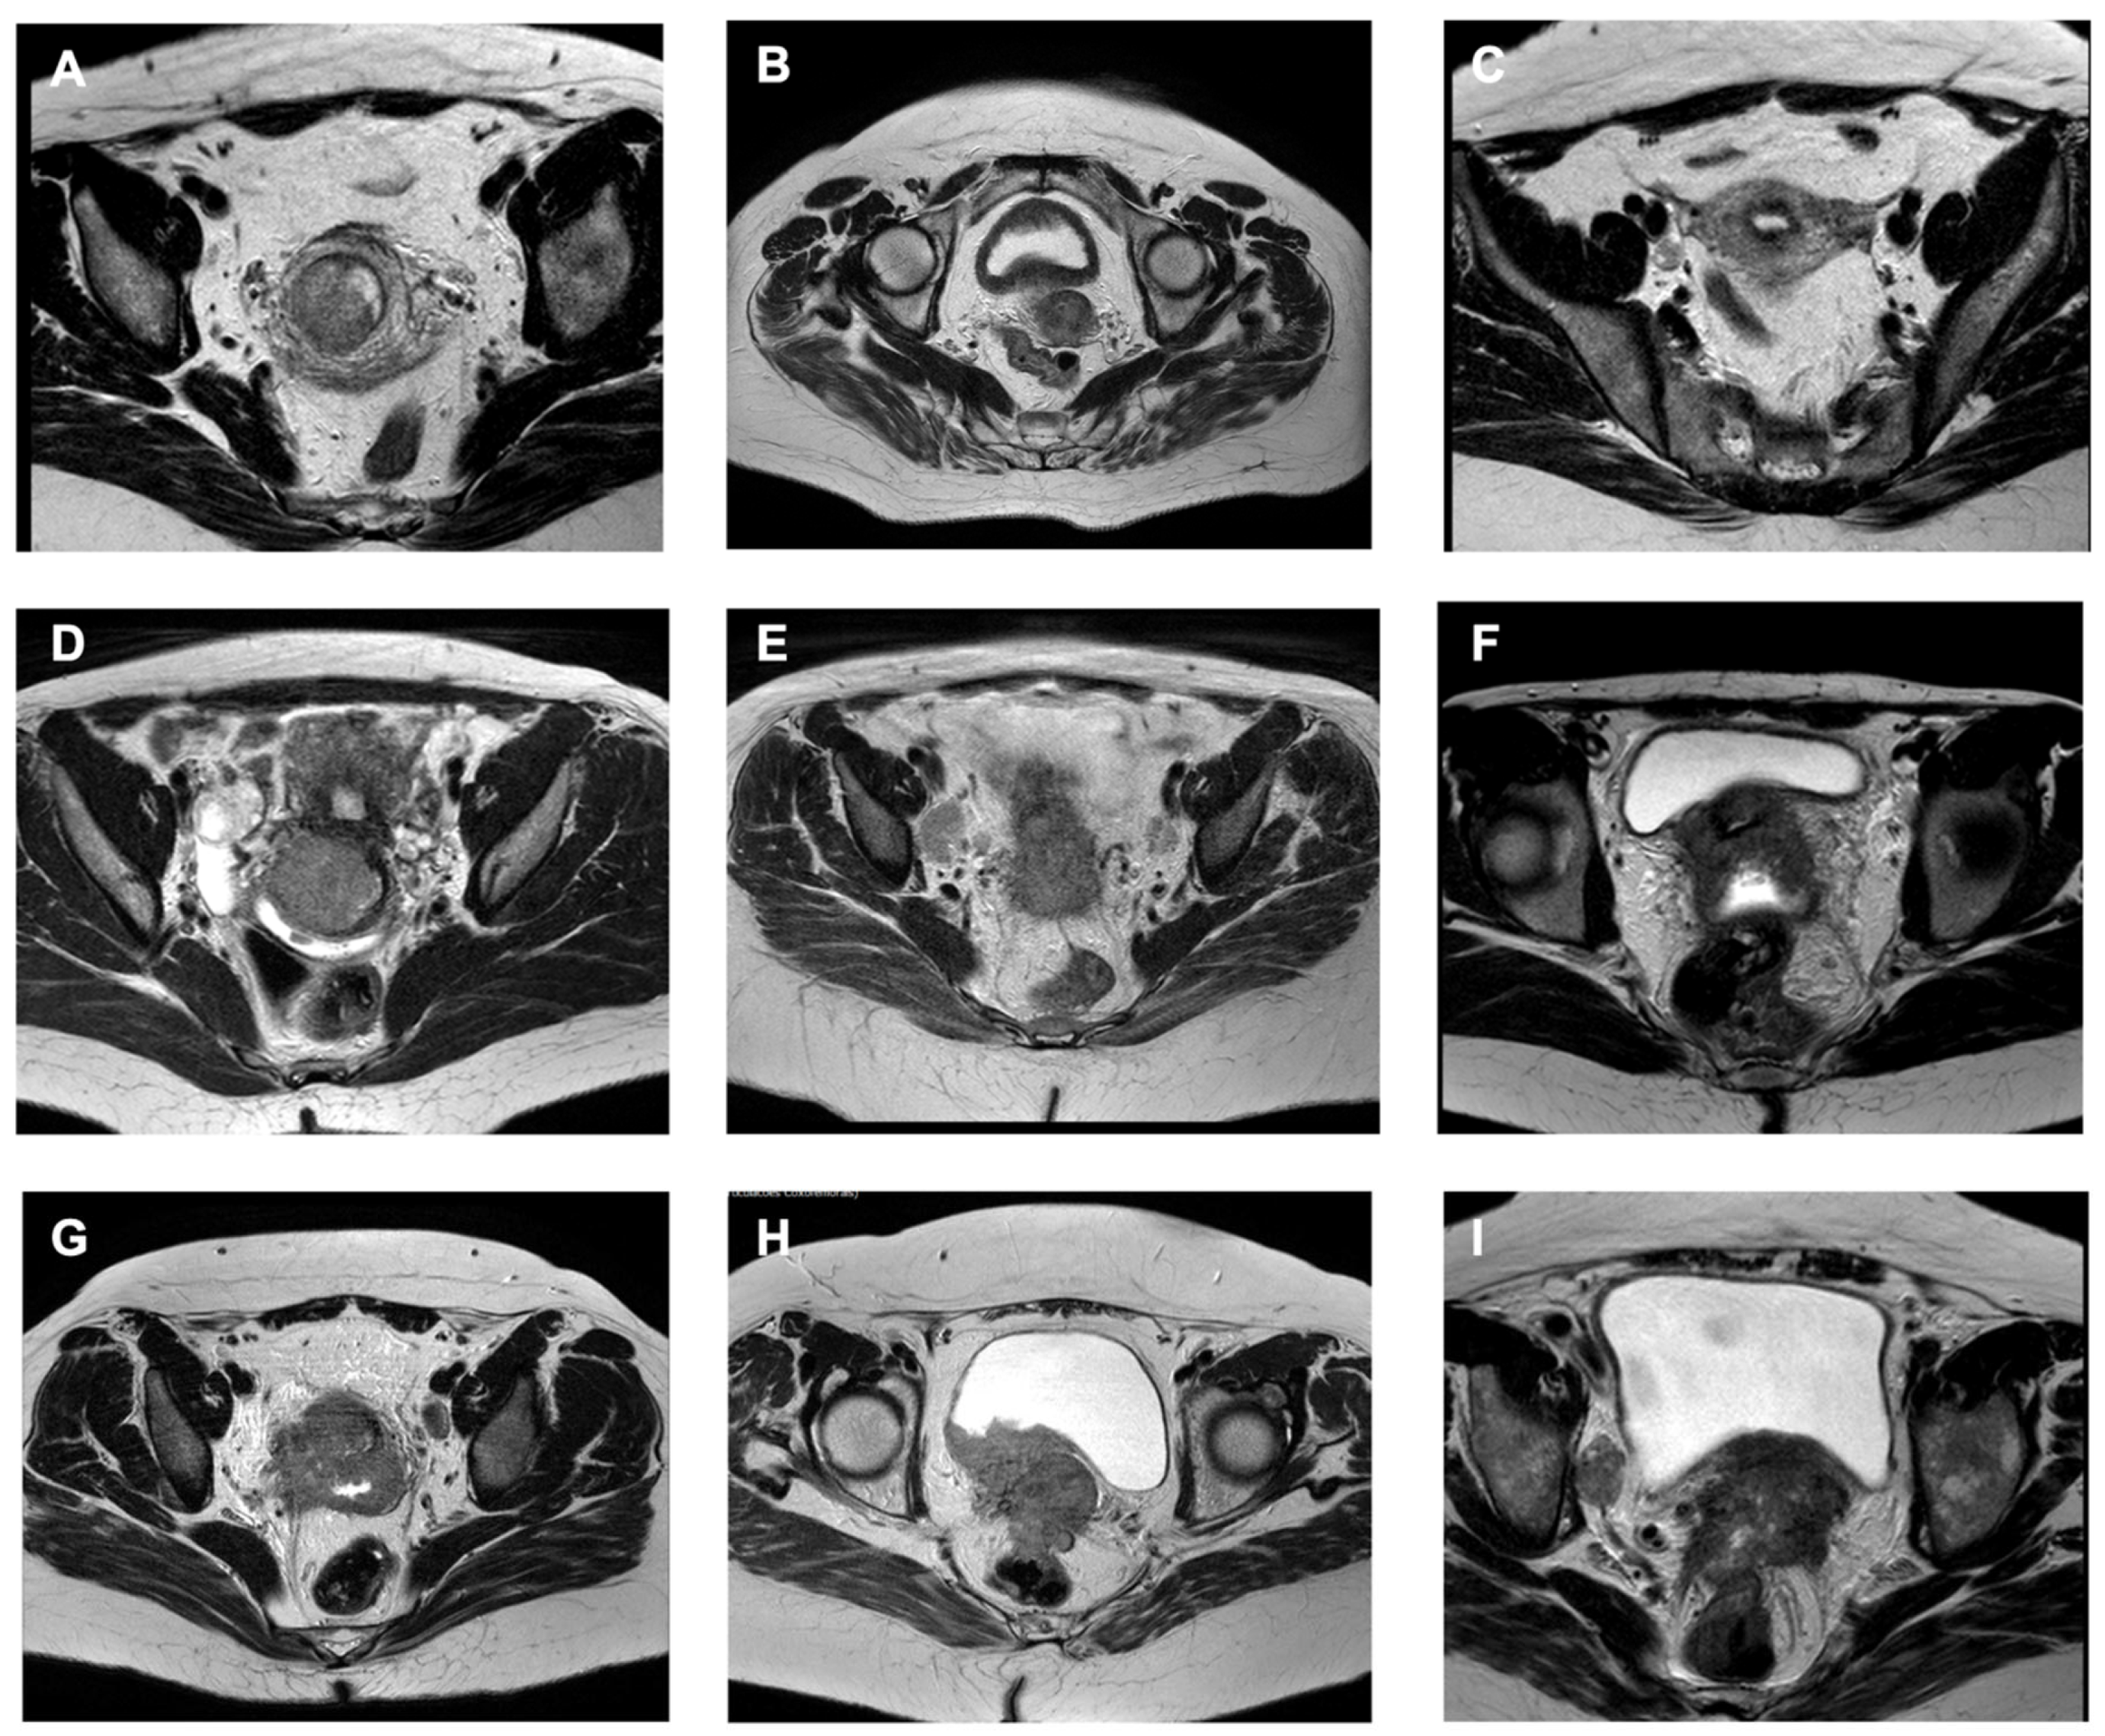

| oT1 | The tumor is limited to the cervical stroma. | The pelvic MRI in the T2 mode shows an uninterrupted dark cervical border zone in both transverse and sagittal planes and no evidence of tumor invasion of the uterine corpus. |

| oT2 | The tumor is limited to the Müllerian compartment (includes cases of initial parametrial involvement limited to the paracervix, without fatty tissue/mesometrium invasion). | Pelvic MRI in the T2 mode can show an interrupted dark cervical border zone in both transverse and sagittal planes, without signs of invasion on urogenital mesentery components (uterine artery with fatty tissue, uterosacral ligaments, bladder mesentery, and inferior hypogastric plexus branches) or bladder adventitia.

| oT3a | The cancer infiltrates any anatomical compartment derived from the Müllerian duct morphogenetic field. | Involvement of any of the following structures:

| oT3b | The cancer infiltrates any compartment matured from the primordial genital tract morphogenetic field. | MRI shows extracervical tumor spread up to the border of the parietal (somatic) retro-, subperitoneum, and peritoneum; endopelvic fascia; and mesorectum, but there is no evidence of infiltration of these tissues. Unilateral or bilateral ureteral dilatation is often present but not obligatory. Tumor involvement of the urethral and bladder wall with or without infiltration of the mucosal layer is often obvious with MRI. Involvement of any of the following structures:

| oT4 | The most advanced ontogenetic local tumor stage is evident if the cancer infiltrates tissues derived from the mesonephric system morphogenetic field, in addition to the oT3b cancer field. oT4 tumors can infiltrate any pelvic and abdominal tissue, except the spinal column and adjacent autochthonous musculature. | Involvement of any of the following structures: